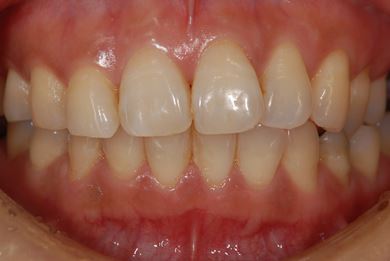

インプラントの症例写真 IMPLANT

骨再生インプラント治療+セラミック治療+歯肉歯槽骨整形

| 性別/年齢 | 女性 / 42歳 | ||||||||||||||||||||||||||||||||

| 主訴 | インプラント治療を受けたい。 | ||||||||||||||||||||||||||||||||

| 治療方針 | 左上奥欠損部分をインプラント治療にて機能的・審美的回復を行う。 | ||||||||||||||||||||||||||||||||

| 治療内容 | インプラント2本(ソケットリフト)、メタルボンドセラミック3本(メタルボンド用土台1本)、歯肉歯槽骨整形 | ||||||||||||||||||||||||||||||||

| 総治療費 | 1,227,713円 | ||||||||||||||||||||||||||||||||

| 治療期間 | 11ヶ月 |